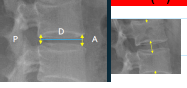

Q what are the names for these measurements? and what is the average + range?

A: Intervertebral Disc Height

assesses the height of the lumbar discs. There are two methods mentioned:

Hurxthal's Method (Right pic.) measures mid-point of body and

Farfan's Method (Left pic.) Uses ratio of anterior (A), Posterior (P) disc heights, and Disc diameter (D).

A/D = Anterior Height Ratio (AHR)

P/D = Posterior Height Ratio (PHR)

Disk height= AHR/PHR.